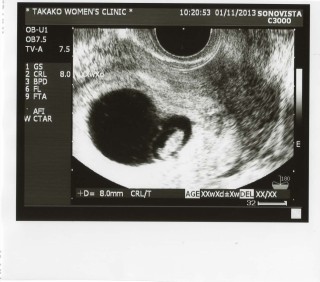

CRL=8㎜

6週に心拍確認出来ましたが

小さな命はちゃんと動いてました♪

次は9週目に検診なのでワクワク・ドキドキです。。